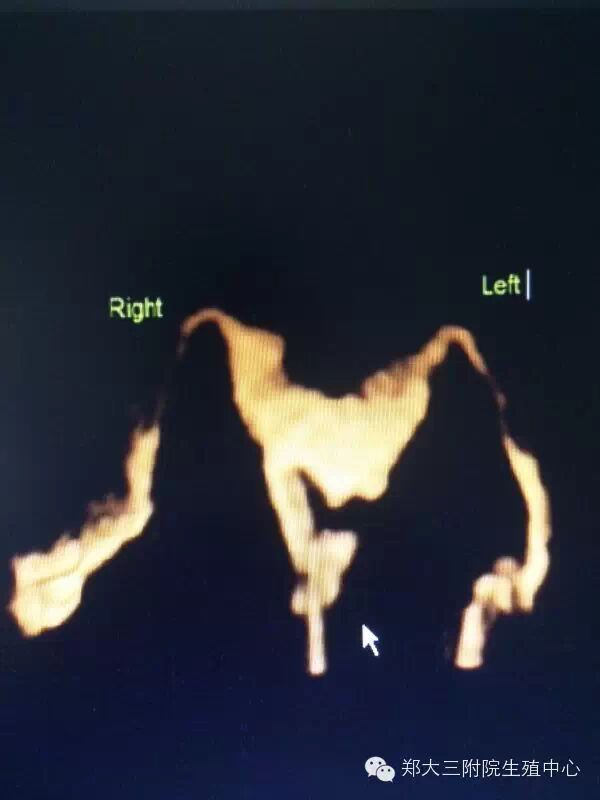

子宫输卵管超声造影(3D/4D-Hycosy)是在三维/四维阴彩下将造影剂经置入宫腔的导管注入子宫和输卵管,显示子宫腔和输卵管形态、位置、以发现宫腔和输卵管内病变、畸形以及评估输卵管通畅性的一种检查方法。

2、图像清晰、可三维立体成像、四维动态录像显示子宫、输卵管、盆腔造影的过程,更直观,便于临床医师观察;

3、对子宫输卵管畸形可明确诊断;

4、对输卵管异常显影如僵硬、扭曲、纤细、角状反折或盘曲的判断更精确;